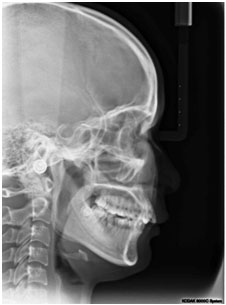

① 科学严谨的牙齿矫正过程首选需要拍摄全景片,构建临床所需的颌面部3D影像,全面了解患者牙槽骨发育情况、牙畸形类型、牙周情况等,这些重要的数据是开展牙齿矫正项目、制定矫正方案所必须的诊治辅助手段。活动期间您可享受免费的全景机拍片检查,通常在其他专科医院需要80-150元不等的费用。详情点击咨询》》》

全景机侧位片